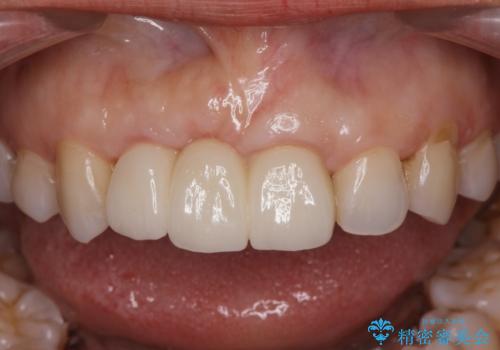

歯周外科をおこなったことで歯ぐきのラインを整え、脱離しないような前歯のブリッジを作製することができました。